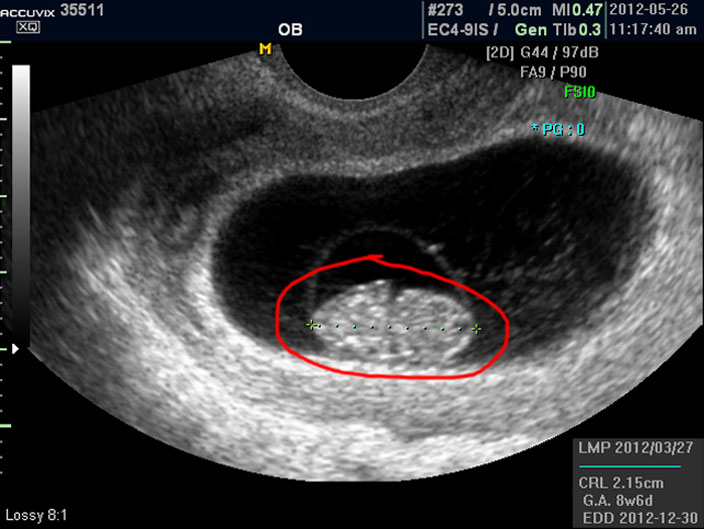

우선 첫번째로 보이는 사진에서 가운데 하얗게 보이는 것이 태아입니다.

우측이 머리 부분이고 좌측이 몸통 부분이며 초기 임신에서는 아기 머리가 몸통의 반정도로 상당히 큰 상태입니다.

태아의 크기는 우측 하단에 실제 크기가 나와 있지만 아래 사진에서 빨갛게 표시한 부분의 안에 보이는 눈금이 1cm입니다.

이런 기준이나 지표들이 표시되는 것은 초음파 장비마다 조금씩 차이가 있고 위치도 다르지만 대개 비슷한 모양이라 한가지를 알면 다른 기종에서도 감상에 그리 어렵지는 않습니다.

상기 이미지는 정지 이미지이기 때문에 심장 움직임과 같은 것은 설명해 드리지 못했지만 이 시기에 중요하게 확인해야 할 점의 하나는 심장 박동의 유무와 횟수입니다.

태아의 심장 박동은 성인보다는 매우 빨라서 보통 분당 120회에서 160 정도 되는 것이 정상입니다.